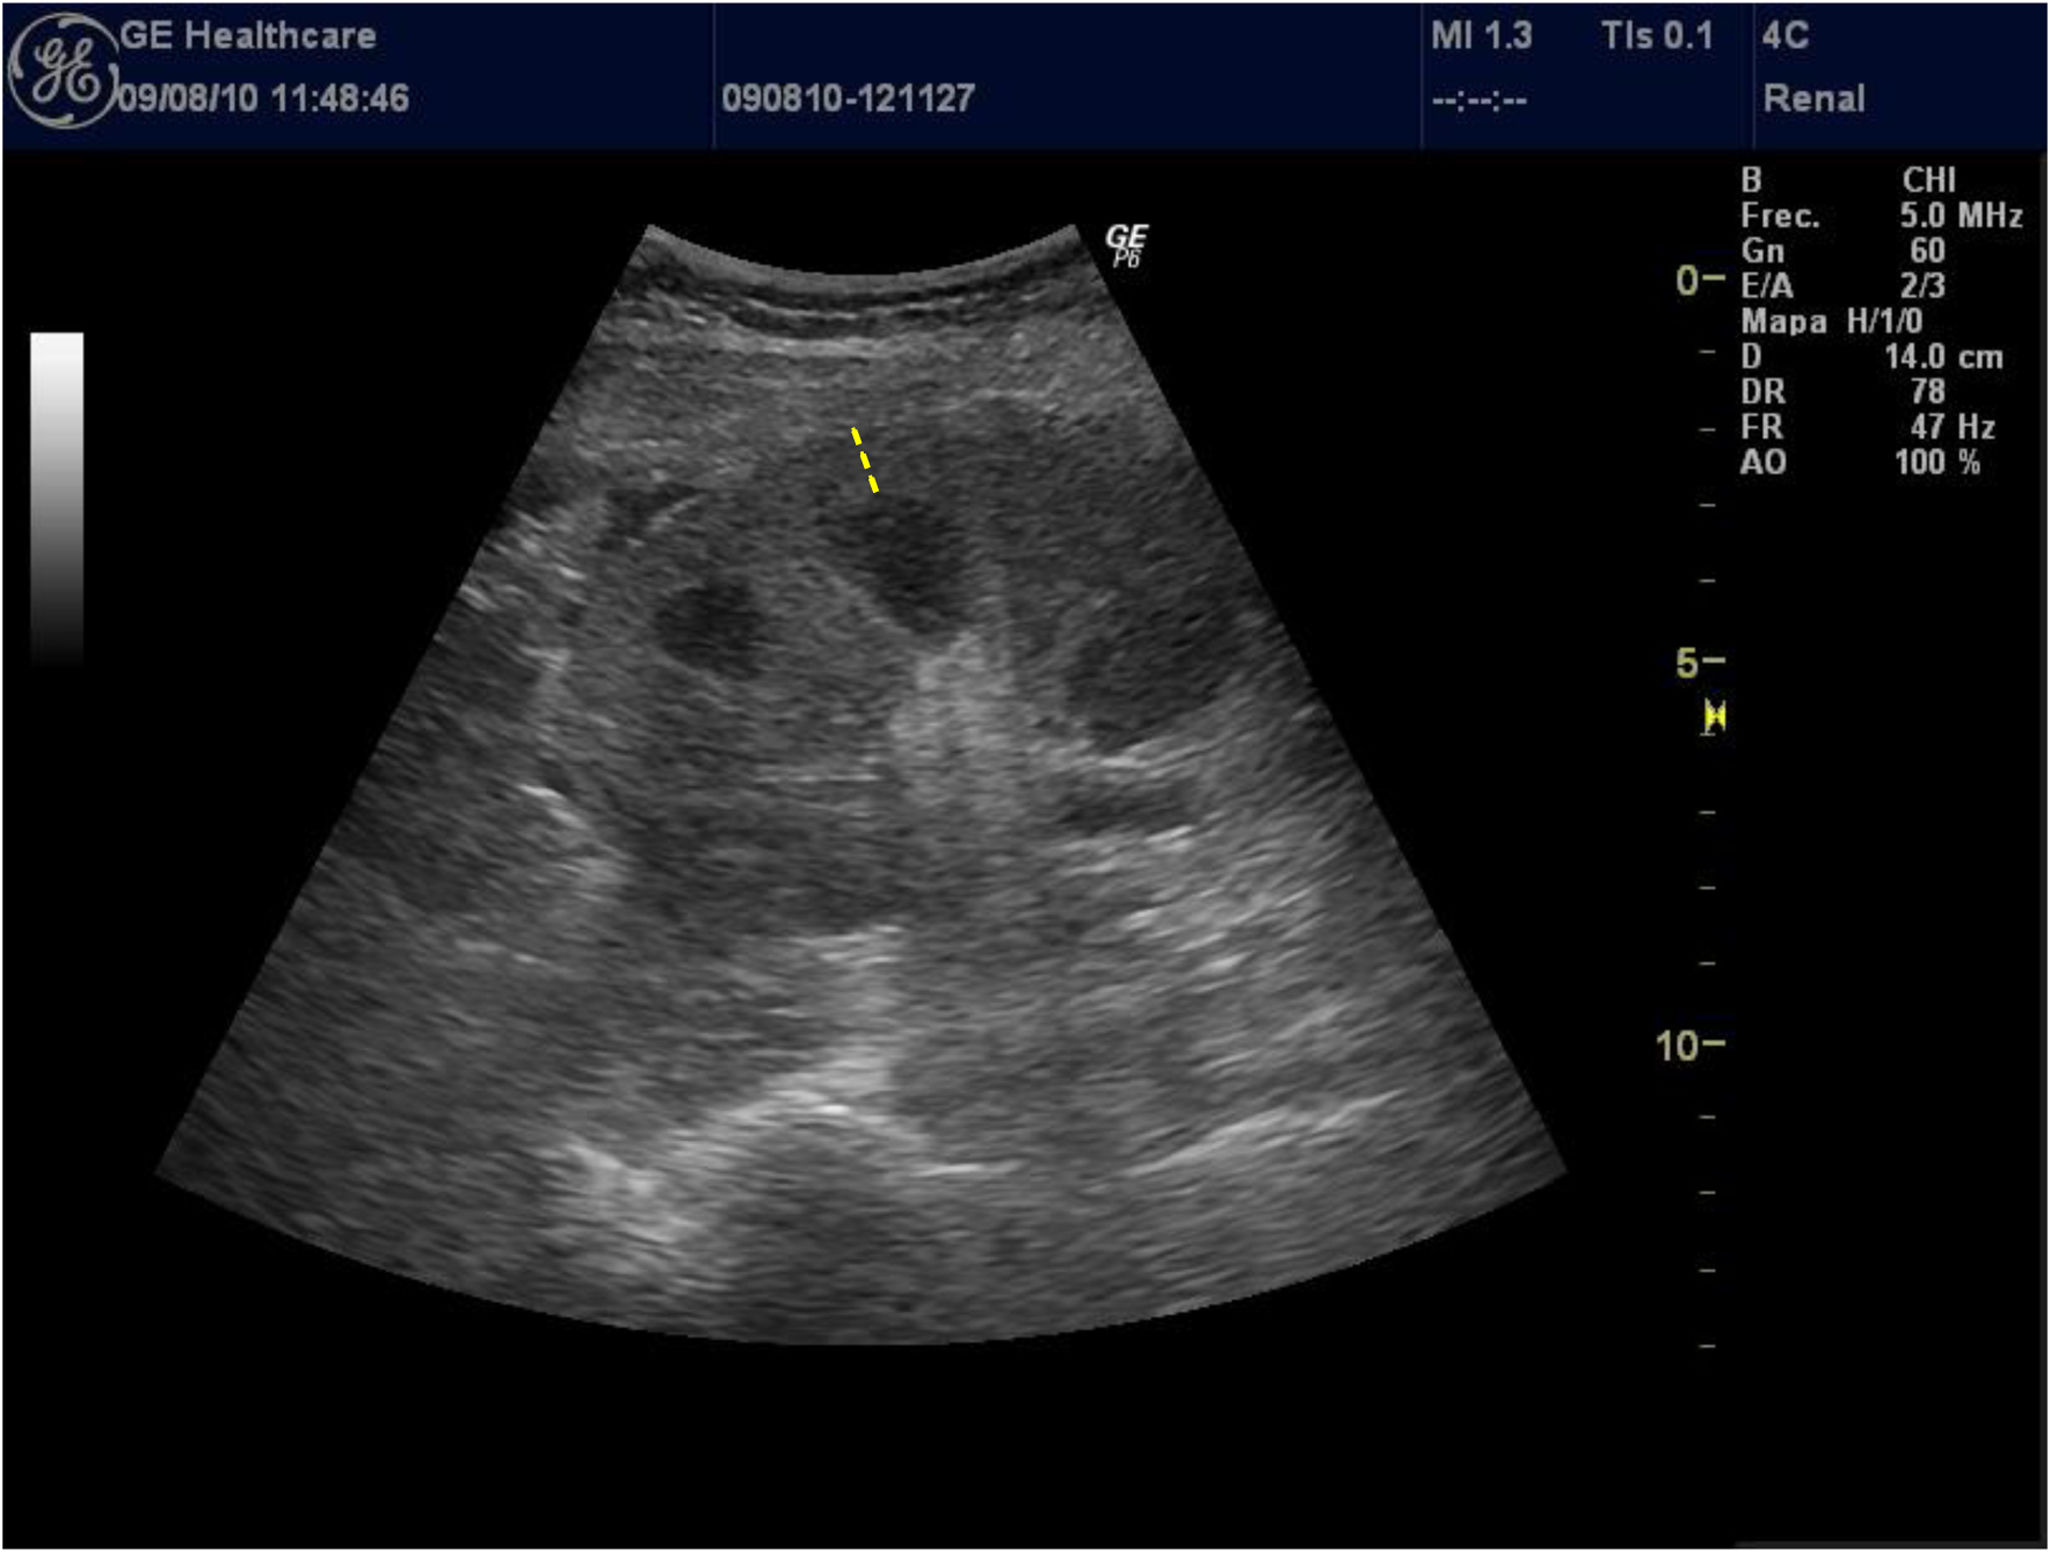

The thickness of the renal cortex is rarely used by researchers because of the difficulty of measuring it in patients with poor corticomedullary differentiation, which is relatively common in patients with advanced CKD. Given that this interface is difficult to identify, reproducibility in related measures is low, and so few studies use it; this translates to a lack of consistent data on the association between renal cortical thickness and impaired renal function. Similarly, Beland et al.13 demonstrated that the thickness of the cortex was closely correlated with the eGFR (Fig. 2).

Figure 2.

Low-frequency convex probe (3.5–5 mHz) placed between the medial axillary line and the posterior axillary line. Longitudinal plane of the left kidney. Dotted line: Cortical thickness (from the base of the renal pyramid to the renal capsule).